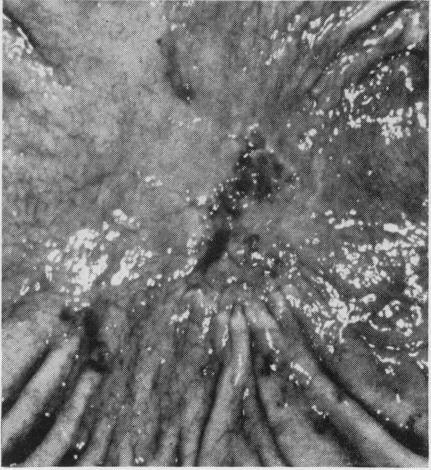

Solanke T F, Kumakura K, Maruyama M, Someya N

Gut. 1969 Jun;10(6):436-42. doi: 10.1136/gut.10.6.436.